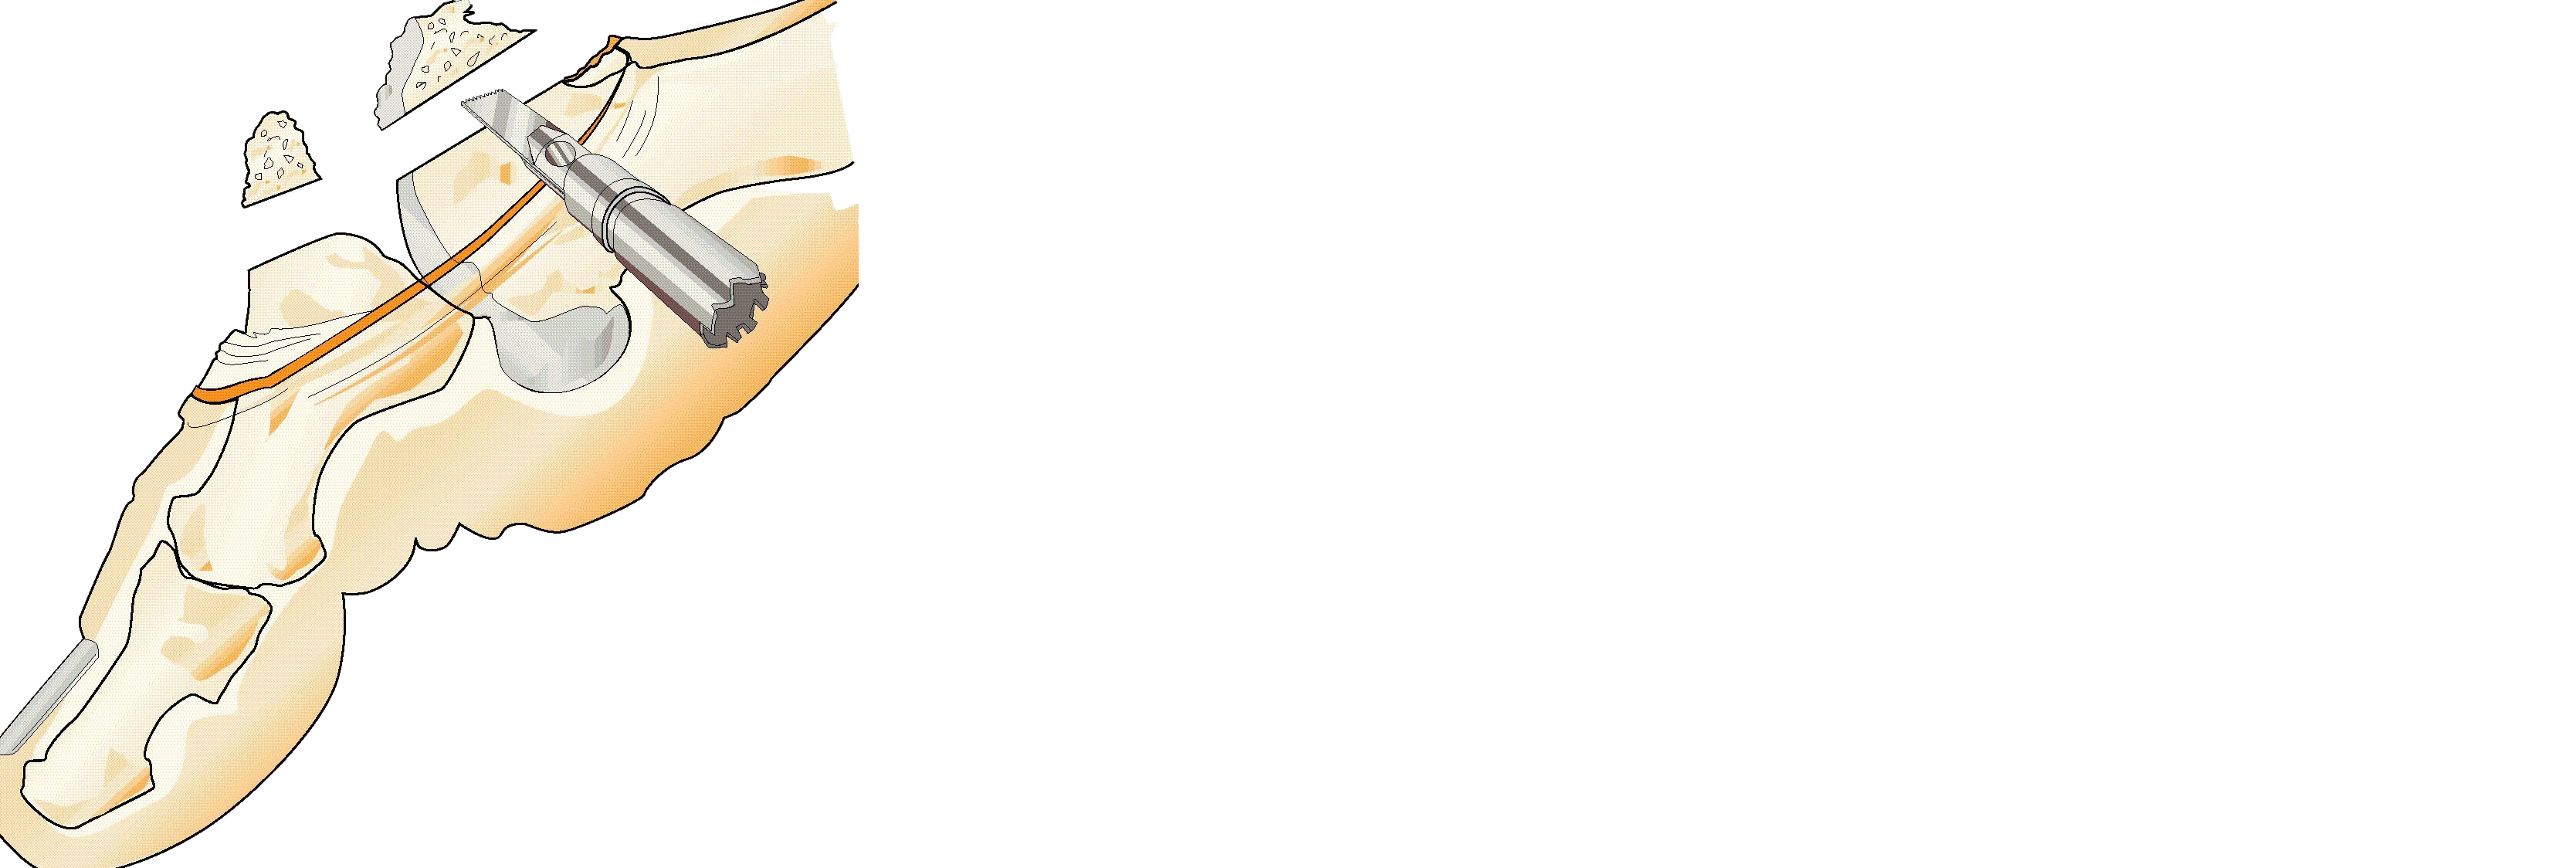

Kirurgisk behandling

När kirurgisk behandling är indicerad rekommenderas tre operationsmetoder beroende på grad av artros, patientens besvär och individuella behov [12][13]

- cheilektomi [14][15]

Cheilektomi |

Mobilisering av leden genom rensning av ledkapsel och borttagning av osteofyter runt leden |

≤ Grad 3. |